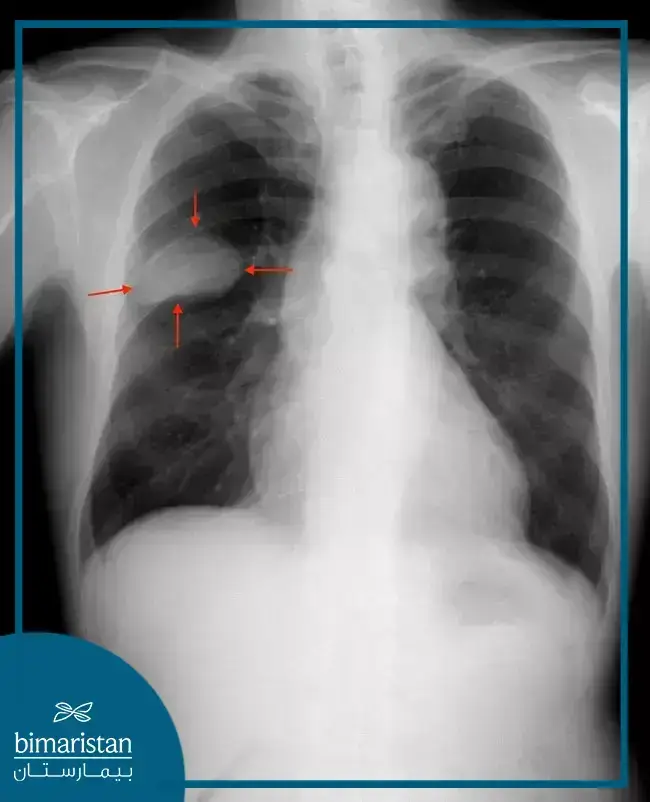

คุณเอ๋ พรทิพย์ ตรวจพบมะเร็งปอดจากการที่เธอมีอาการเสียงแหบและไปตรวจร่างกายอย่างละเอียด แม้ว่าเสียงแหบอาจไม่ใช่สาเหตุโดยตรง แต่ก็เป็นจุดเริ่มต้นที่ทำให้เธอไปพบแพทย์ คุณเอ๋เข้ารับการทำ CT scan ซึ่งเผยให้เห็นก้อนเนื้อบริเวณปอดด้านซ้ายหลังหัวใจ ซึ่งเป็นตำแหน่งที่ X-ray ทั่วไปอาจมองไม่เห็น ก้อนเนื้อของคุณเอ๋มีขนาดประมาณ 2-3 เซนติเมตร จัดอยู่ในระยะที่ 1 (น่าจะ 1b)